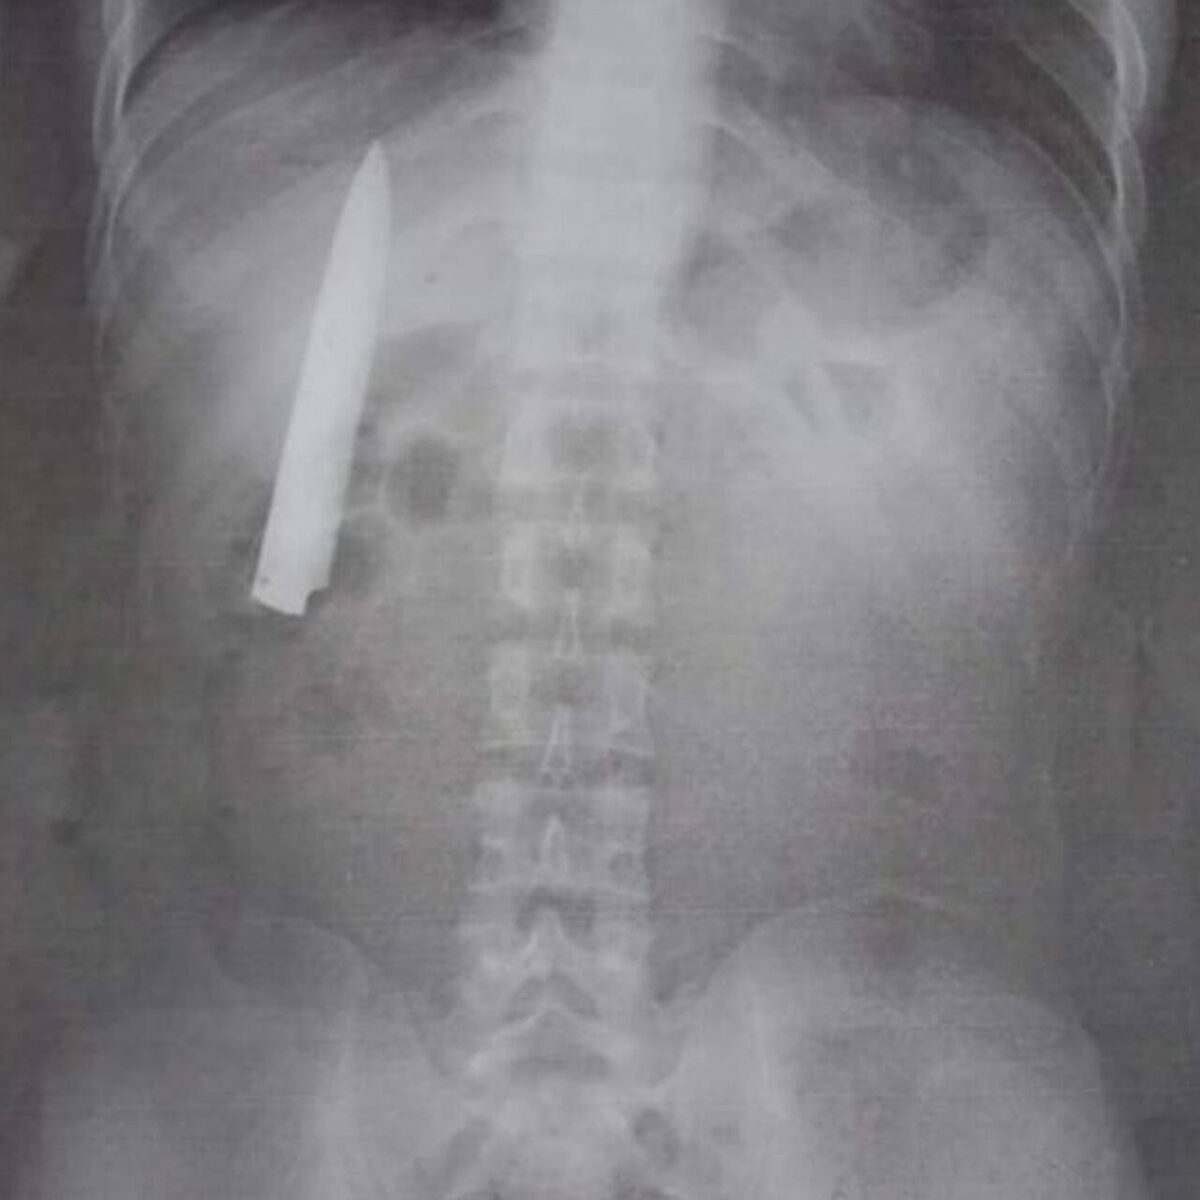

фото из интернета. Инородное тело грудной клетки.

только вместо клинка ножа, я вижу отломок ножниц (от места соединения до конца режущих частей, сомкнутые). Я повторно его спрашиваю, так откуда рубец? И он поведал историю: "около полугода назад, выпивали с приятелями, кому-то показалось, что водку разлили не поровну, завязалась ссора, в ходе которой, приятель воткнул ему в спину ножницы, они сломались, кольца остались в руке у приятеля, а концы в полости грудной клетки гр. Б. К врачам он не обращался, покашлял неделю, а через пару недель и рана затянулась. Кореша сдавать в ментовку он тоже не планировал, меж друзей всякое бывает (орфография гр.Б сохранена)." Под кожей этот инородный предмет не пальпировался (прощупывался), ранение вероятнее всего было проникающим в плевральную полость. Надо отметить, что гр. Б ведёт разгульный образ жизни, не работает, склонен к конфликтам и практически постоянно находится под наркозом (в состоянии алкогольного опьянения).